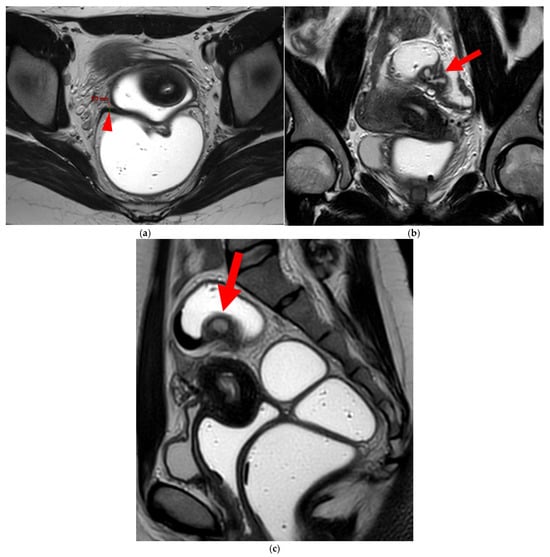

2.3.1. “Kissing Ovaries”: A Form Straddling Between Type 5B and Type 6 USLs

Besides endometriomas, another type of ovarian involvement in DIE includes adhesions that cause the ovaries to retract medially across the midline, behind the uterus, into the pouch of Douglas. When the ovaries are displaced medially and are in close proximity, they are commonly referred to as “kissing ovaries”. Additionally, medialized ovaries on preoperative imaging expose the digestive tract to a 20% risk of involvement [22]. In our experience, the injection of a contrast agent is useful when there is doubt about an endometriotic rectosigmoid invasive lesion on T2WI, especially if a rectal filling was not performed. A markedly enhancing mucosa, which outlines rectosigmoid local wall thickening on post-contrast T1WI without fat suppression (forming a “medallion-shaped” lesion), is a valuable aid to diagnosis.

In the HTD MRI classification of USLs, the “kissing ovaries” sign is considered a form between types 5B and 6. In the case of concomitant rectal involvement, the USL is classified as type 6 (Figure 15); otherwise, it is classified as type 5B (comparable to a nodule with spiculated margins).

Figure 15. Pelvic MRI scan of a patient with a “kissing ovaries” sign and rectal involvement (i.e., HTD type 6 USLs). (a,b) Axial T2WI (a) and contrast-enhanced T1WI (b) show both ovaries in close proximity (“kissing ovaries” sign) (arrowheads) and rectosigmoid wall infiltration (arrows). (c) Sagittal contrast-enhanced T1WI shows rectosigmoid wall infiltration, appearing as a “medallion-shaped” lesion outlined by markedly enhancing mucosa (arrowhead).

Diagnostics 15 01508 g015